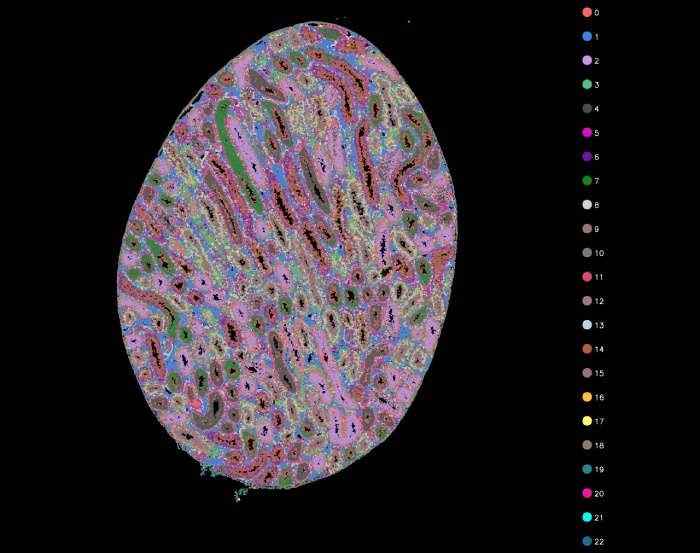

聚類分析

l13-cluster聚類圖

l7-cluster聚類圖

l5-cluster聚類圖